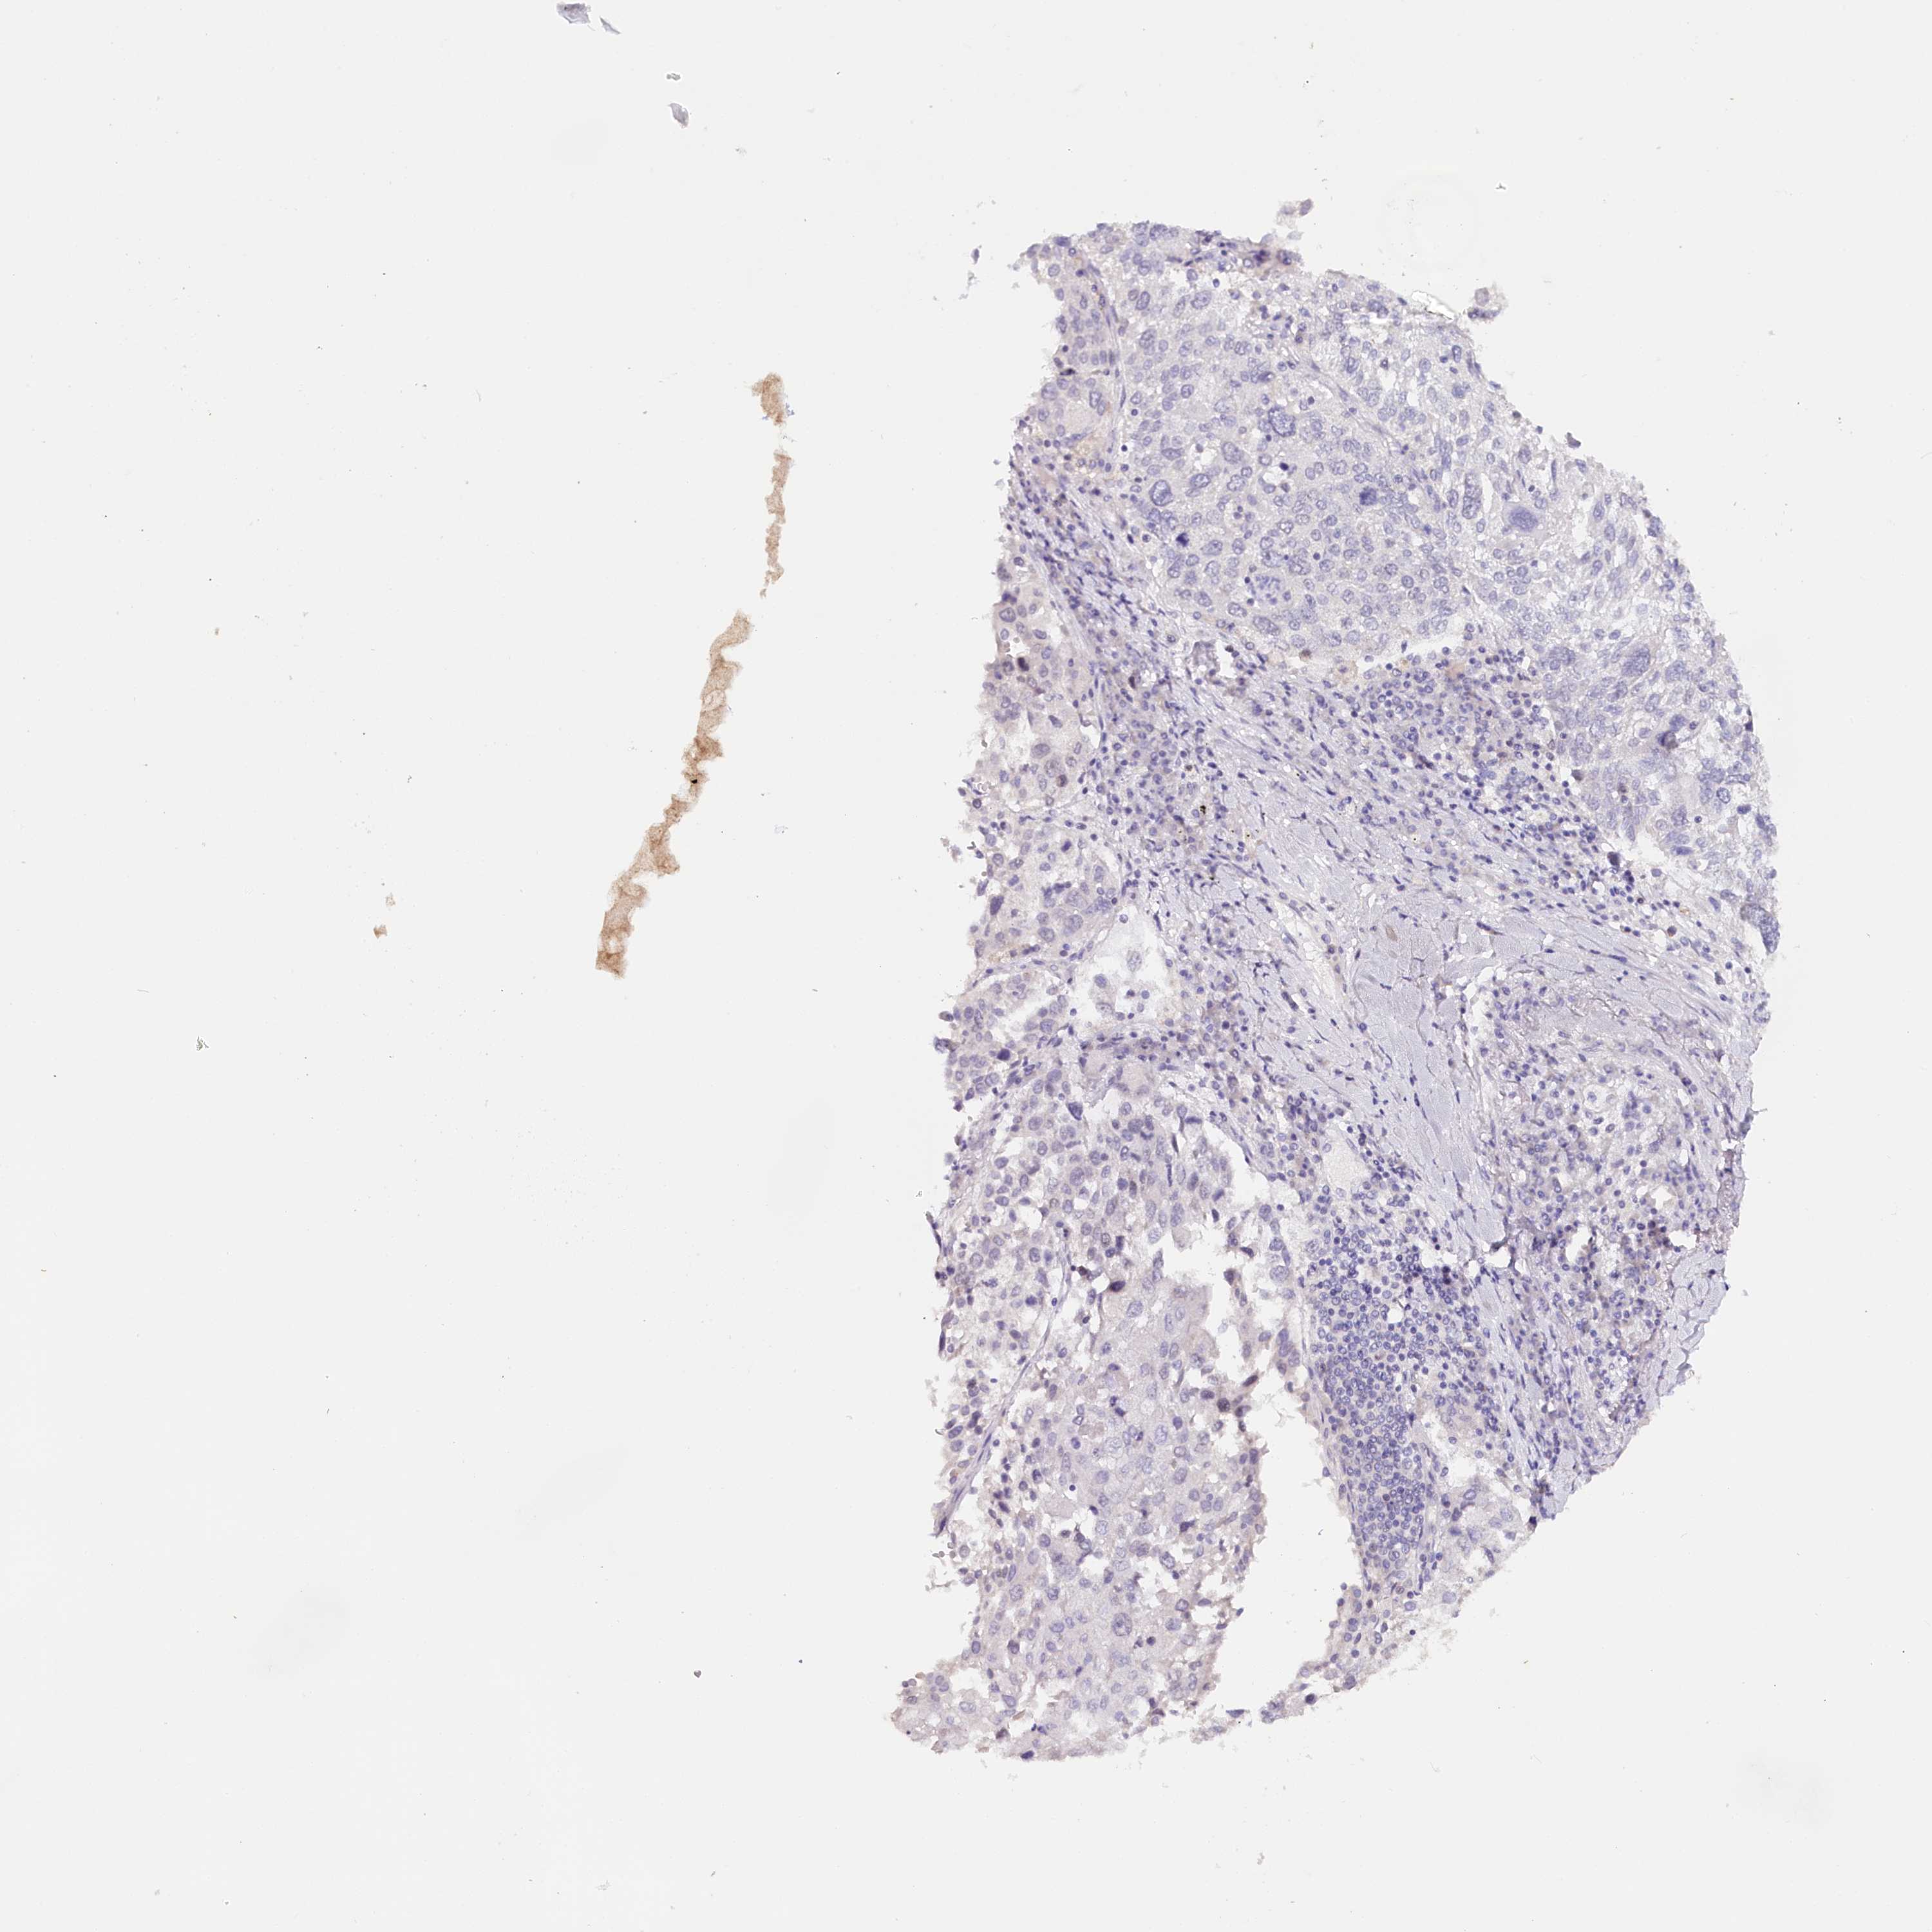

TP53

• CANCER

CANCER LUNG CANCER Show tissue menu